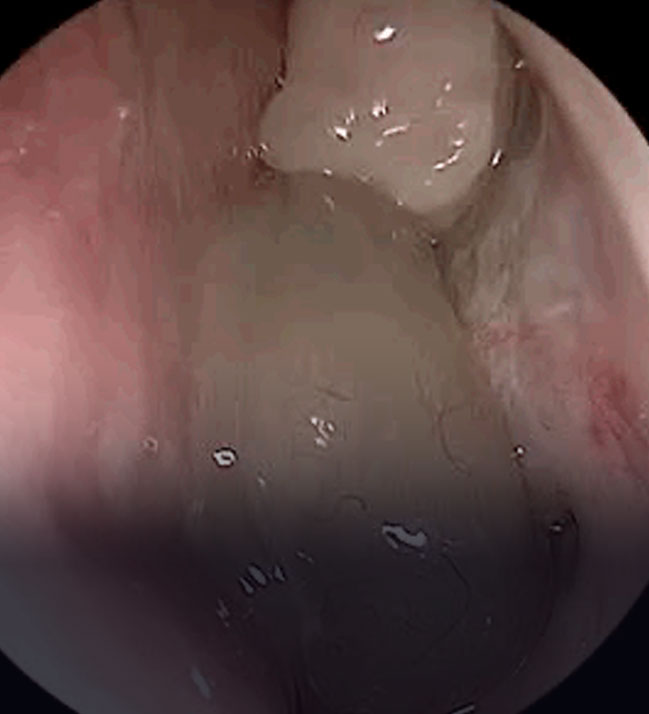

Kronik Sinüzit Ameliyatı

Endoskopik Sinüs Cerrahisi – FESS